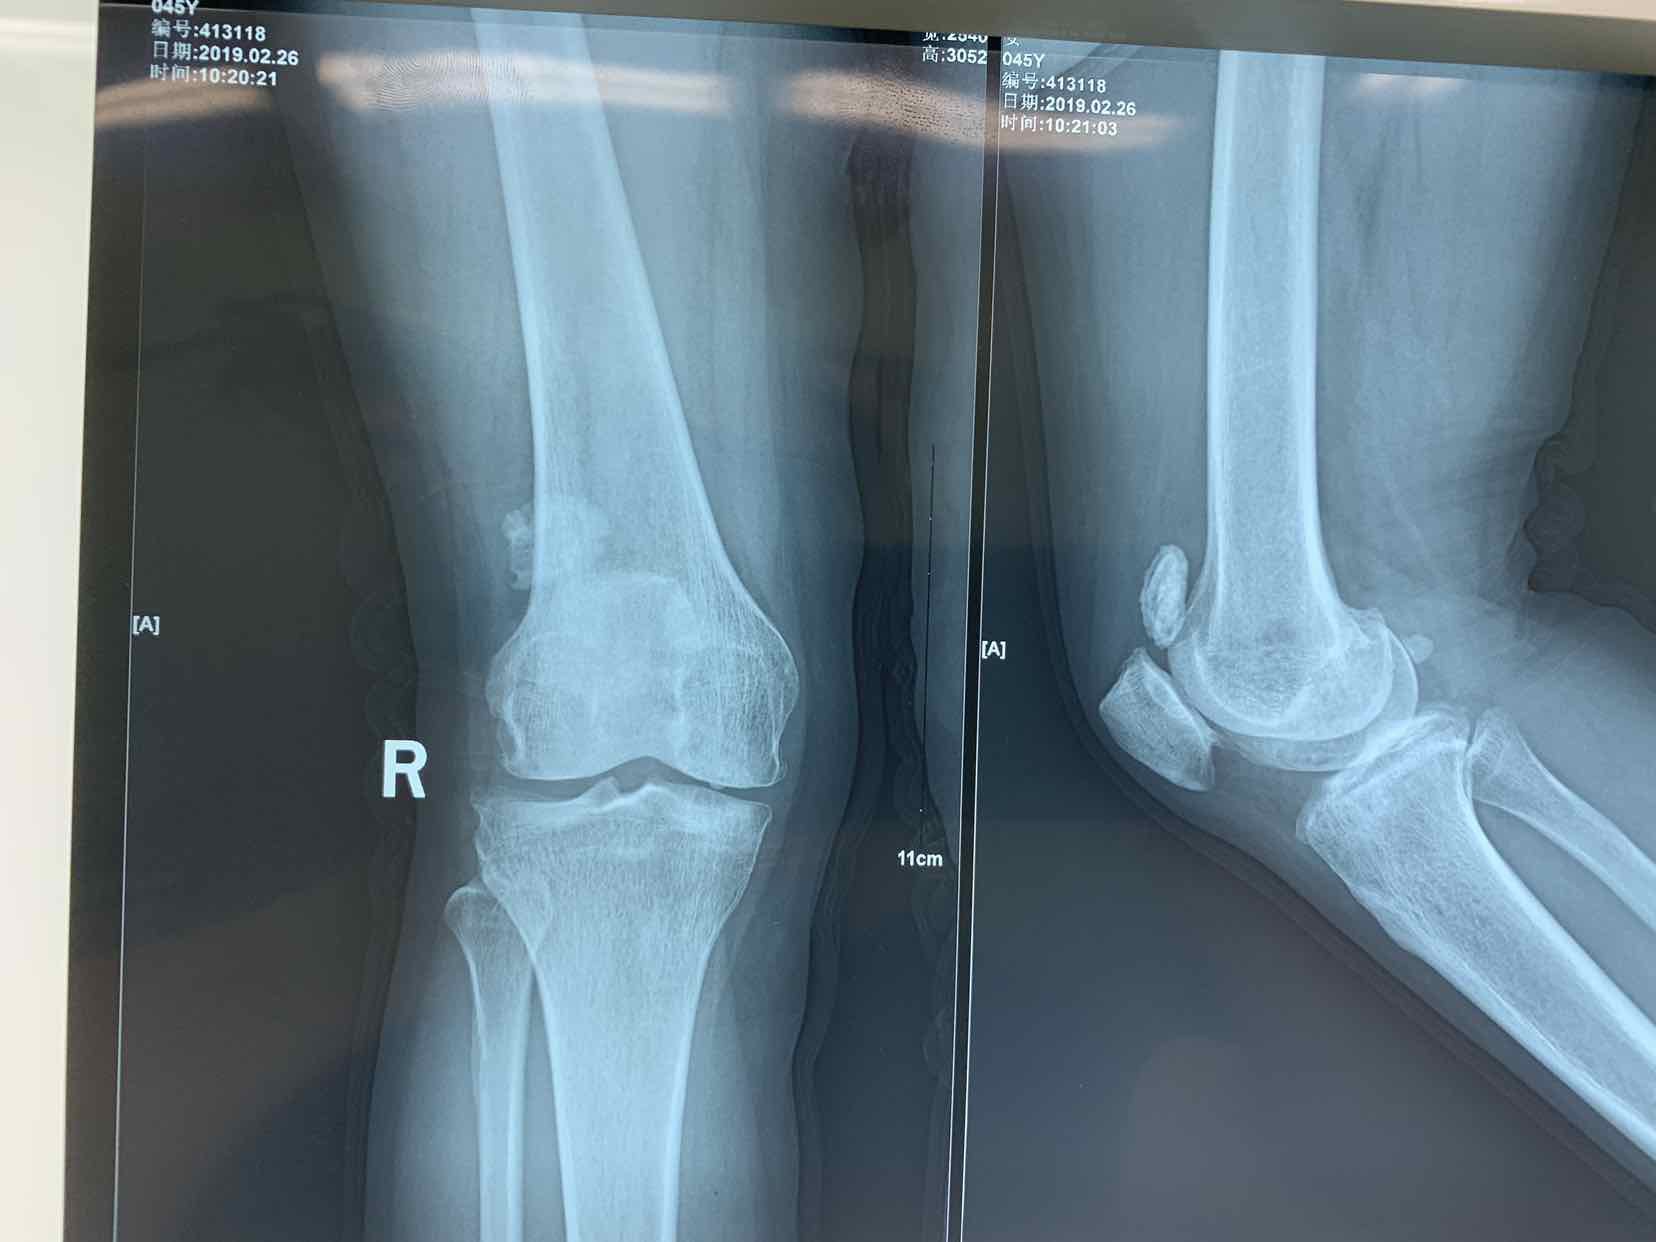

患者因双侧膝关节骨性肿物发现二十余年。收入院。患者无二十余年前无明显诱因发现双侧膝关节内有骨性肿物。异常活动。偶尔在屈曲活动时出现局部嵌夹于关节内。疼痛。不能活动。并弹响。近半年内肿物增大。疼痛发作频繁。遂来诊。门诊拍片提示见双侧膝关节内骨性游离体,位于关节内。门诊以双侧膝关节游离体收入院。

查体见患者双侧膝关节局部肿胀。压痛。可于局部触及骨性肿物在关节内游走。屈伸活动时偶有嵌顿。行走活动受限。拍片提示双侧膝关节骨性游离体。

诊断为双侧膝关节游离体。再局麻下银行膝部游离体取出术。术后患者恢复良好。

膝关节游离体是临床常见疾病。可以通过关节镜探查发作。拍片或者核磁共振检查也可获得可靠诊断。处理非常简单。发现肿物挤压至一侧。切口就可以取出。